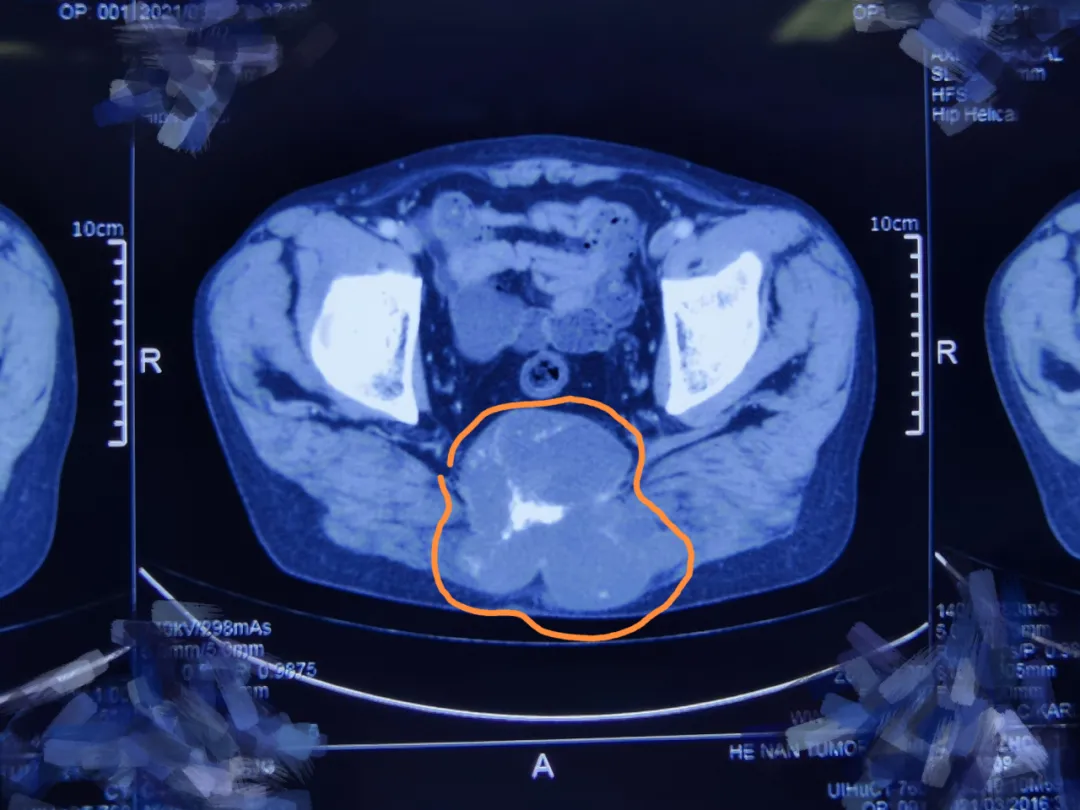

因为病灶巨大,达12厘米×9厘米,不仅破坏了骶骨骨质,还侵犯了双侧臀大肌,解剖位置较深,周围结构复杂,瘤体血运丰富,手术暴露困难,给切除带来了很大挑战。

![]()

△上图可见左右侧臀大肌均受肿瘤侵犯、范围很大